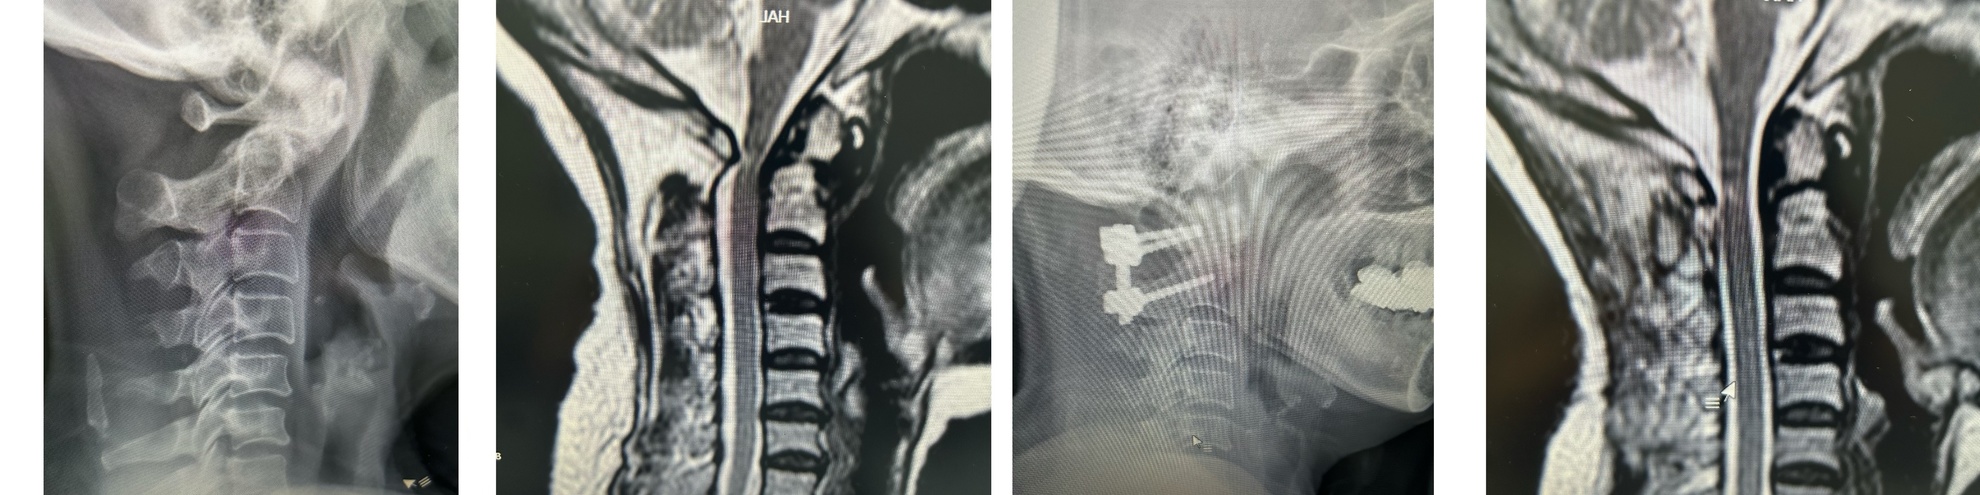

近日,漳州市中医院骨伤微创病区范纯泉博士团队成功实施了我市首例 “天玑” 机器人精准导航辅助下寰枢椎关节融合术。这不仅标志着漳州市中医院在脊柱外科微创手术领域取得了新的里程碑式突破,更意味着闽西南地区脊柱疾病的精准化、微创化治疗迈入全新阶段。

寰枢椎处于颈椎的顶端,与颅底紧密相连,解剖结构极为复杂,周围环绕着丰富的神经、血管等重要组织。因操作空间狭小、对精度要求极高,手术风险高,针对寰枢椎部位的手术历来被视为脊柱外科领域的 “高难度禁区”。

术中,“天玑”凭借高精度的定位系统,实时规划最佳手术路径,将手术误差控制在毫米级范围内。在它的“透视眼”辅助下,范纯泉博士团队的医生们如虎添翼,操作更清晰、更精准、更安全,极大降低了手术对周围正常组织的损伤风险。

术前X线、MRI 术后X线、MRI